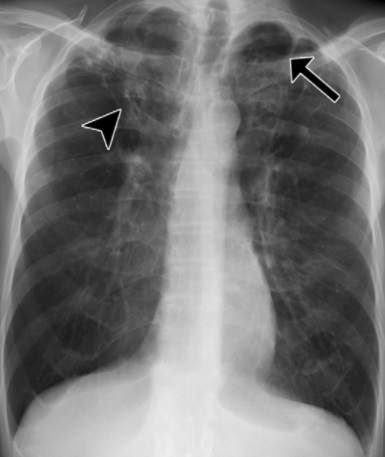

Quando ativada, geralmente em situações de baixa imunidade, a infecção atinge principalmente os pulmões, mas pode comprometer outros órgãos. Isso transforma a tuberculose em uma ameaça constante, ainda que muitas vezes invisível.

Foto: Dr_Microbe/Adobe Stock